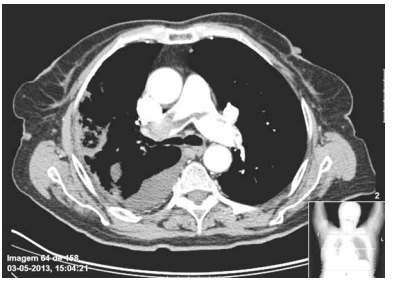

Mulher, 68 anos, sem antecedentes mórbidos, apresenta dor torácica ventilatório-dependente, de forte intensidade com piora à inspiração profunda e dispneia intensa. Recebeu alta há 15 dias após internação para cirurgia de correção de fratura de colo de fêmur. Exame físico: bom estado geral, taquipneica leve, afebril, PA = 120x70 mmHg, saturação periférica de oxigênio = 89% em ar ambiente, ausculta cardíaca normal e ausculta pulmonar com estertores crepitantes finos em bases. Realizados eletrocardiograma e tomografia computadorizada de tórax com contraste, ilustrados a seguir.

enunciado 505633-1

enunciado 505633-2

Assinale a alternativa que contém a causa fisiopatológica mais provável da intercorrência apresentada.

enunciado 505632-1

enunciado 505632-2

enunciado 505631-1

enunciado 505631-2

Considerando os achados clínicos e de exames complementares, assinale a alternativa que contém a abordagem terapêutica correta.